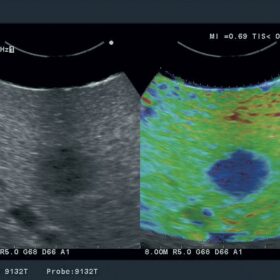

- Real-time Tissue Elastography

- Real-time Tissue Elastography